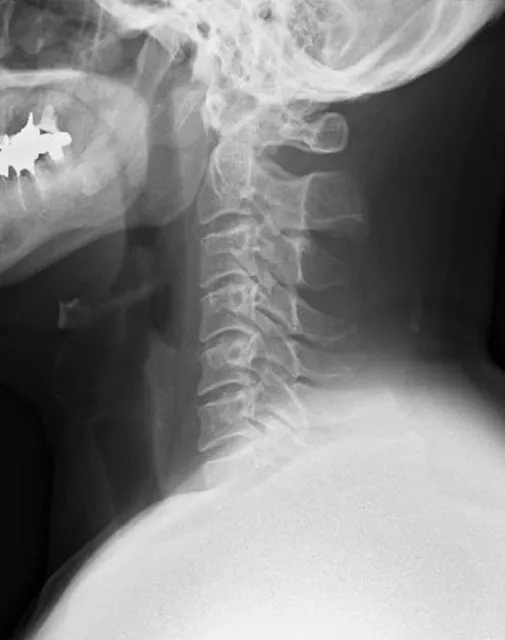

実際に報告されているリスクとしては、筋肉や靭帯の損傷、関節の炎症、まれに神経障害などが挙げられます。特に首周辺の施術は注意が必要で、過度な力を加えられると頭痛やめまい、しびれなどの症状が出ることもあります。これらの危険性は、施術者が患者の身体の状態や既往歴を十分に把握していない場合に高まります。

実際の施術内容は、問診・触診により身体の状態を評価し、背骨や関節の歪みを手技で調整するというものです。これにより、神経機能の正常化や筋肉のバランス改善を図ることが目的とされています。ただし、急性の疾患や重篤な症状がある場合は、必ず医療機関での診断を受ける必要があります。